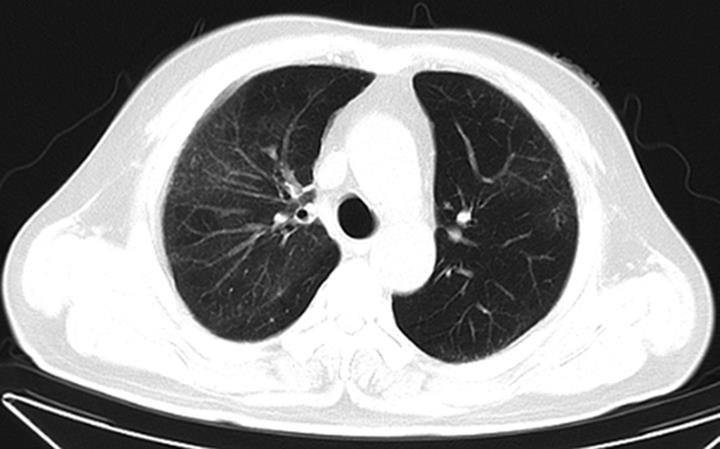

摘要:目的 探究显微镜下多血管炎(microscopic polyangiitis,MPA)肺受累的临床特征与预后因素分析。方法 回顾性分析2014年1月1日至2021年3月1日于重庆医科大学附属第一医院确诊及随访至2022年3月1日的237例MPA肺受累患者临床资料。采用Kaplan-Meier方法和Cox比例风险回归模型分析生存数据,得出累积生存率及预后因素。结果 MPA肺受累患者的平均年龄是65.18岁,中位随访时间为26.13个月。在纳入研究的237例患者中,MPA伴弥漫性肺泡出血(diffuse alveolar haemorrhage,DAH)患者98例(41.35%)。MPA肺受累患者1年、3年、5年累积生存率分别为67.50%、54.10%、43.00%。中位生存时间为45.03(0.10,97.73)个月。MPA伴DAH患者1年、3年、5年累积生存率分别为63.30%、49.40%、40.20%。Cox多因素回归分析显示年龄>65岁(HR=1.981,95%CI=1.244~3.154,P=0.004)、白细胞总数(white blood cell,WBC)>10×109个/L(HR=1.860,95%CI=1.170~2.956,P=0.009)、血清肌酐(serum creatinine,sCr)>250 μmol/L(HR=1.987,95%CI=1.217~3.243,P=0.006)、氧合指数<300 mmHg(HR=2.780,95%CI=1.696~4.557,P<0.001)、诊断时第三版伯明翰血管炎活动性评分(Birmingham vasculitis activity score version 3,BVASv.3)(HR=1.040,95%CI=1.006~1.075,P=0.020)是影响患者生存时间的独立预测因素(P<0.05)。结论 MPA肺受累患者生存率低下,年龄>65岁、WBC>10×109个/L、sCr>250 μmol/L、氧合指数<300 mmHg、诊断时BVASv.3是MPA肺受累预后不良的独立危险因素。